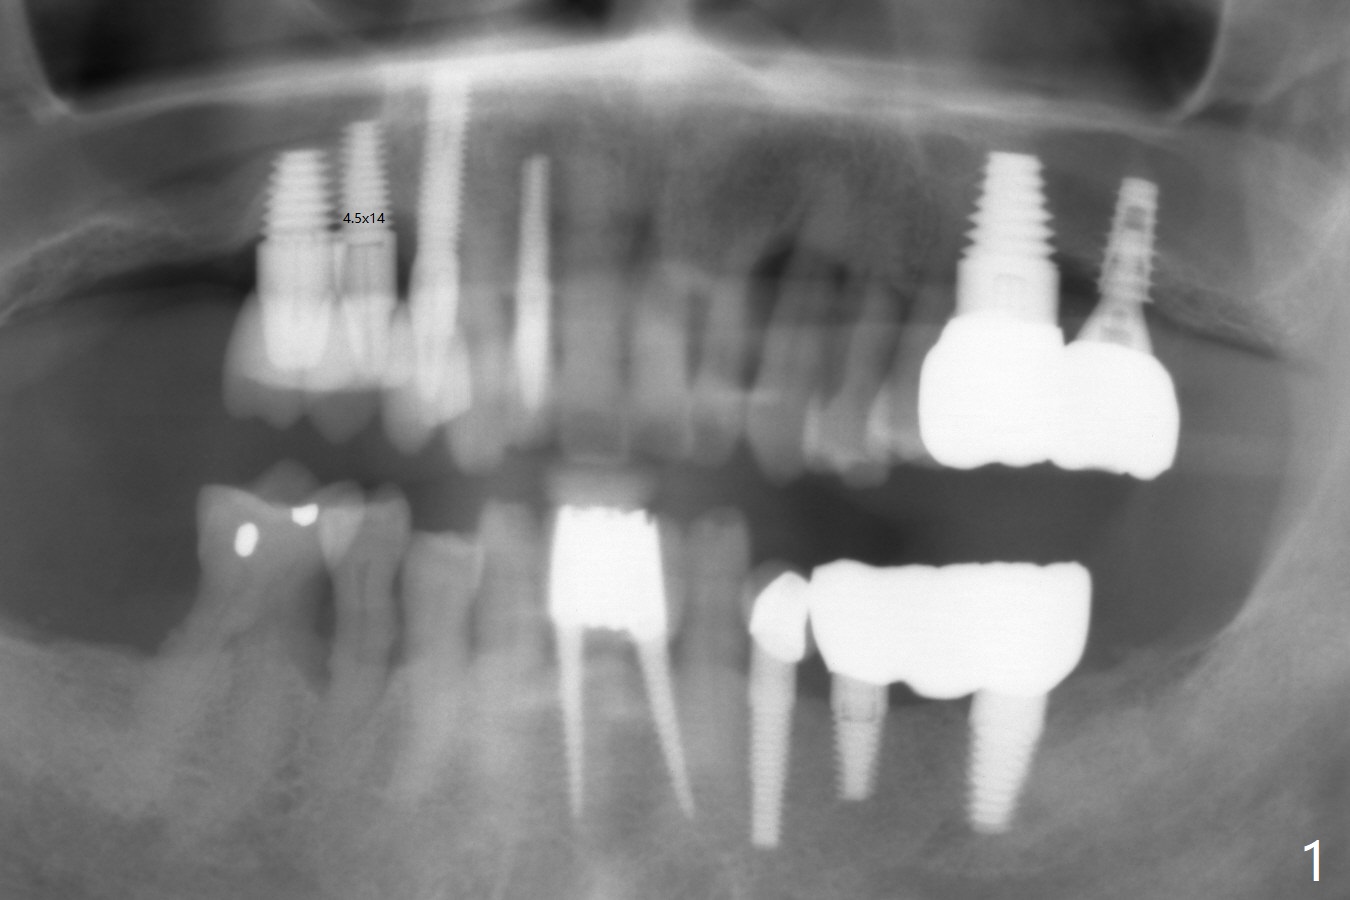

A 60-year-old man develops periimplantitis at #3-5 (Fig.1).  After failure of two rounds of bone graft, the implant at #4 is removed with bone graft 3.5 months earlier.  The infection resolves.  Before the implant removal, there is no gingiva between #4 and 5.  It appears that these 3 implants are placed too close to each other and/or they are too large.  To prevent recurrent infection, a 2.5 or 3.0 mm implant will be placed.  Take preop PA.  Incision will be made.  If the bone is narrow buccopalatally, use 1 and 1.5 mm microosteotomes to initiate osteotomy.  Also prepare Tatum 1- and 2-piece implants (3.5 mm).